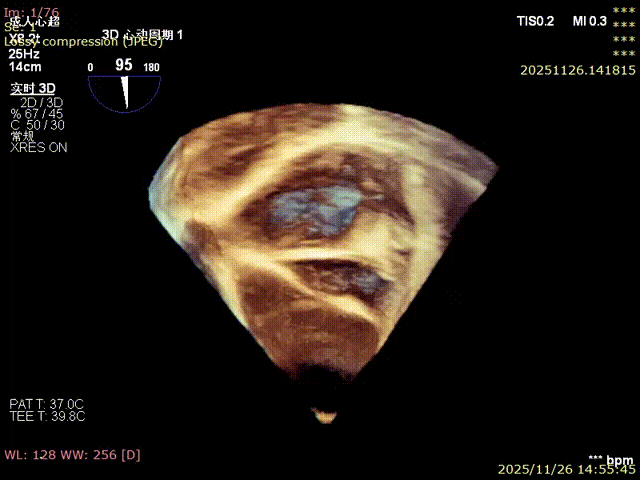

3D image

Annulus area: 16.2 cm²

Annular area: 11.0 cm² (1100 mm²)